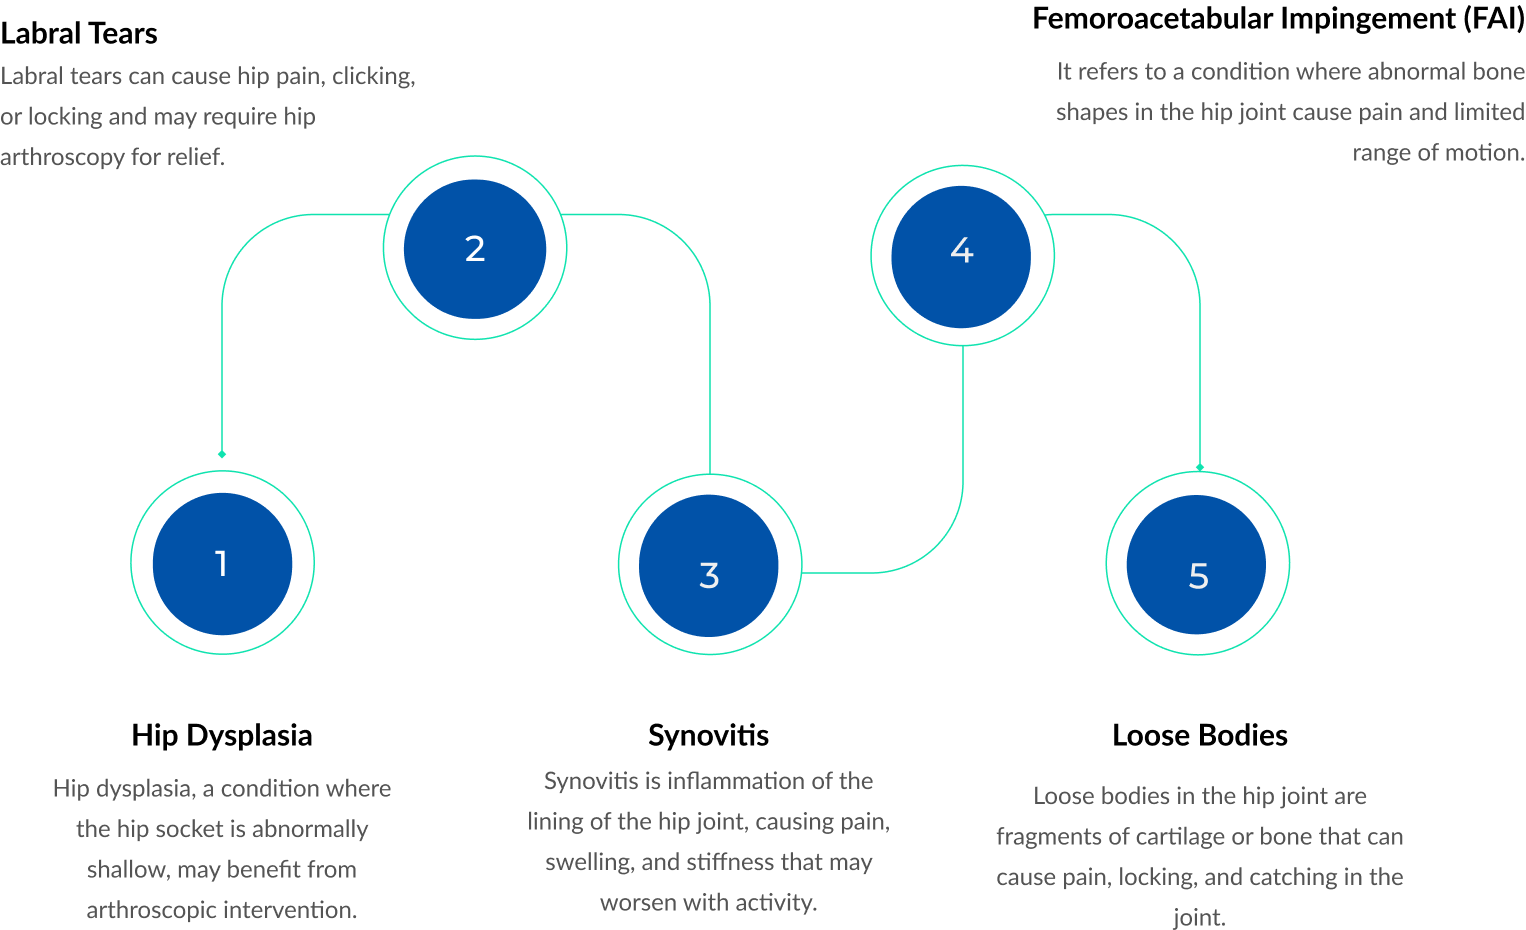

Hip joint arthroscopy is a minimally invasive surgical procedure that involves the use of a small camera and instruments to diagnose and treat various hip joint conditions. It is commonly used to address issues such as hip impingement, labral tears, cartilage damage, and loose bodies within the joint.

Those who may benefit from this procedure include